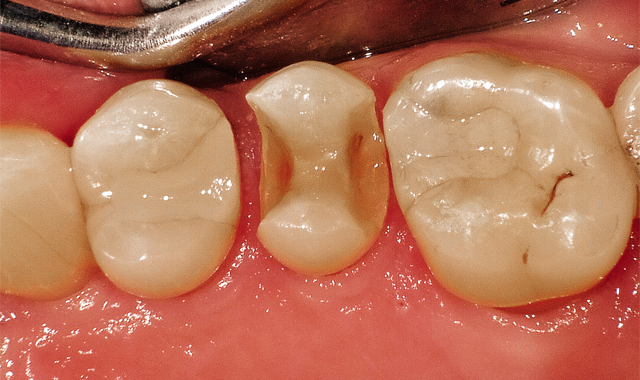

The challenge: Easy to onlay, easier to crown, far more of a challenge to place a direct restoration (Fig. 1).

In Case 1, it was a challenge to place a direct restoration.